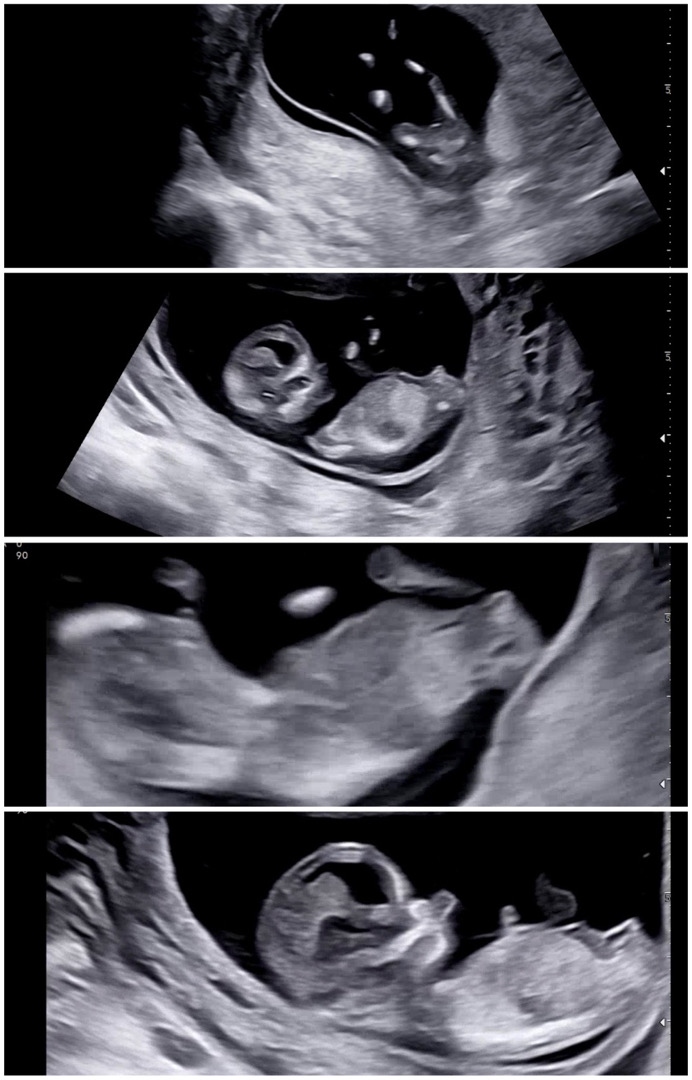

고수님들 각도법 같이 봐주세요 🥹

어떤사진은 아들같구 어떤사진은 딸 같은데 저는 하나도 모르겠네요😂😂 사실 태몽도 떨이라 저랑 남편 둘다 딸을 기대하고있거등요..🤭 아들이어도 넘 좋지만…!! ㅎㅎㅎ 아직 12주 3일차라 확실하진 않지만 저랑 비슷한데 아들이나 딸이었던 분들 답변 남겨주시면 감사하겠습니댜🙏🏻😊